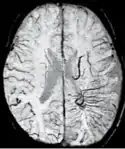

The detection of micro-hemorrhages, shearing, and diffuse axonal injury (DAI) in trauma patients is often difficult as the injuries tend to be relatively small in size and can be easily missed by low resolution scans. SWI is usually run at relatively high resolution (1 mm3) and is extremely sensitive to bleeding in the gray matter/white matter boundaries making it is possible to see very small lesions increasing the ability to detect more subtle injuries.